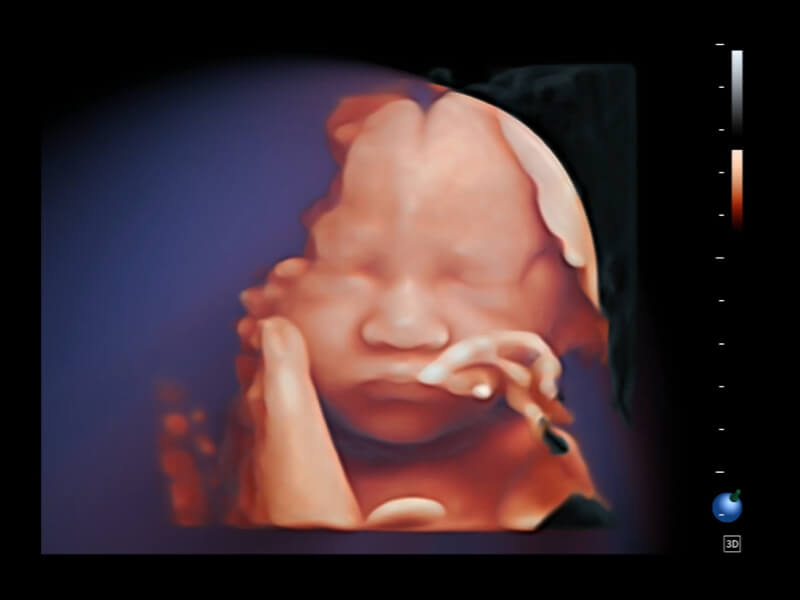

夢(mèng)溪?P80以“關(guān)愛(ài)女性”為基石,提供全方位的解決方案,量身定制以滿足女性的健康需求,涵蓋婦科、生殖健康檢查、產(chǎn)前篩查及產(chǎn)后康復(fù)等領(lǐng)域。

作為開(kāi)立醫(yī)療全新打造的超高端旗艦超聲產(chǎn)品,從探頭抬起喚醒開(kāi)啟掃查到多維探頭發(fā)射接收,通過(guò)先進(jìn)的場(chǎng)成像發(fā)射、自適應(yīng)聚合重建等技術(shù),基于RF Data原始射頻數(shù)據(jù)在圖像生成、高端功能等方面實(shí)現(xiàn)突破,為婦產(chǎn)科、兒科提供全方位臨床解決方案。